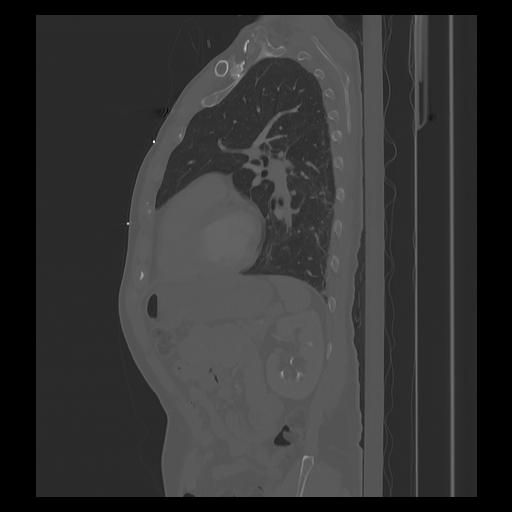

33 PULMON,CE,Sagittal,3.000,PULMON,Sagittal,